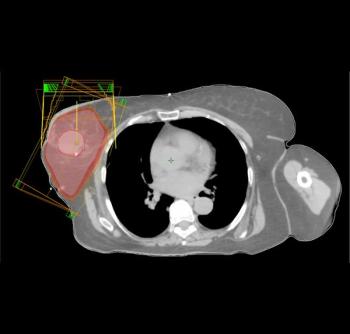

Adjuvant radiation therapy after lumpectomy improves survival for elderly women with early-stage, triple-negative breast cancer, according to a study to be presented at the 2015 ASCO Breast Cancer Symposium.

The exposure of the heart to radiation during radiotherapy for ductal carcinoma in situ (DCIS) did not increase cardiovascular mortality or morbidity, according to a study by researchers in the Netherlands.